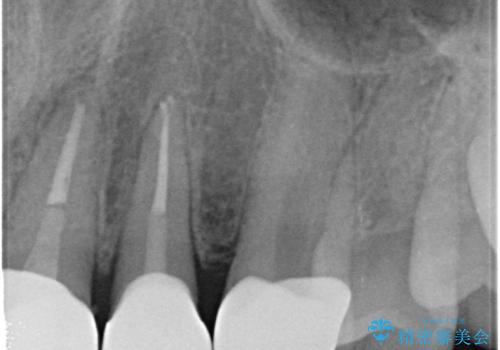

歯の神経の状態を見たところ、前歯3本とも神経が死んでしまっていました。

根の治療を行い、ぐらつきに関しては様子を見て連結をするとのお話をさせていただきました。

結果ナイトガードの使用によりぐらつきはだいぶ回復してきたため連結はしていません。